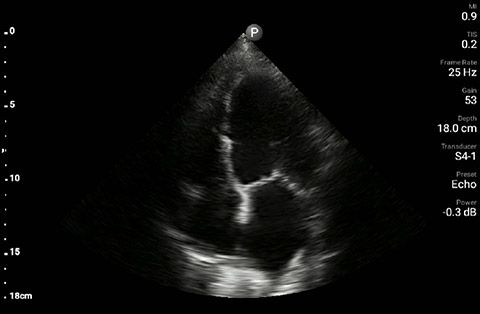

The patient had reduced LV systolic function without new or severe valvular pathology, a dilated, non-collapsing IVC, and diffuse B lines (left greater than right) on lung ultrasound imaging.

Apical 4-chamber

A 69 year-old male with a known history of hypertension, chronic non-oliguric kidney disease, insulin dependent diabetes, and chronic systolic heart failure with an ejection fraction (EF) of 25% secondary to ischemic cardiomyopathy was recovering in the CardioVascular ICU after four vessel coronary artery bypass grafting. His post-operative course had been complicated by acute respiratory failure, acute on chronic non-oliguric renal failure, delirium and pseudomonas pneumonia. The patient’s oxygenation had been improving on antibiotic therapy with aggressive diuresis and ionotropic support, although his BUN and creatinine remained quite elevated. Family had been reluctant to initiate dialysis given his clinical improvement and ability to make urine with diuretic support. The patient was extubated to high-flow oxygen by nasal cannula after successfully passing a spontaneous breathing trial, although, he had failed extubation one week prior secondary to acute dyspnea and hypoxia. Two days later, the patient began to have a fever, worsening shortness of breath with increased oxygen requirements, and inability to wean ionotropic and vasopressor support further. Because of concern for septic shock, the patient was given a total of 500ml of crystalloid overnight. Whole blood lactic acid levels returned at 1.6, serum creatinine increased from 5.8 to 6.11, and the patient’s fever and shortness of breath worsened. Repeat cultures were obtained and antibiotic therapy was broadened further while initiating non-invasive positive pressure ventilation for acute respiratory distress. In the interim, while awaiting laboratory results and chest X-ray imaging, POCUS with a three-point exam (F-TTE, IVC collapsibility, and lung ultrasound) was used for bedside evaluation of the etiology of the patient’s dyspnea. Within minutes, and with the additive information from the combined cardiac, subcostal IVC, and lung ultrasound imaging, the patient was diagnosed with acute on chronic congestive heart failure and flash pulmonary edema as the cause of his respiratory distress and hypoxia.